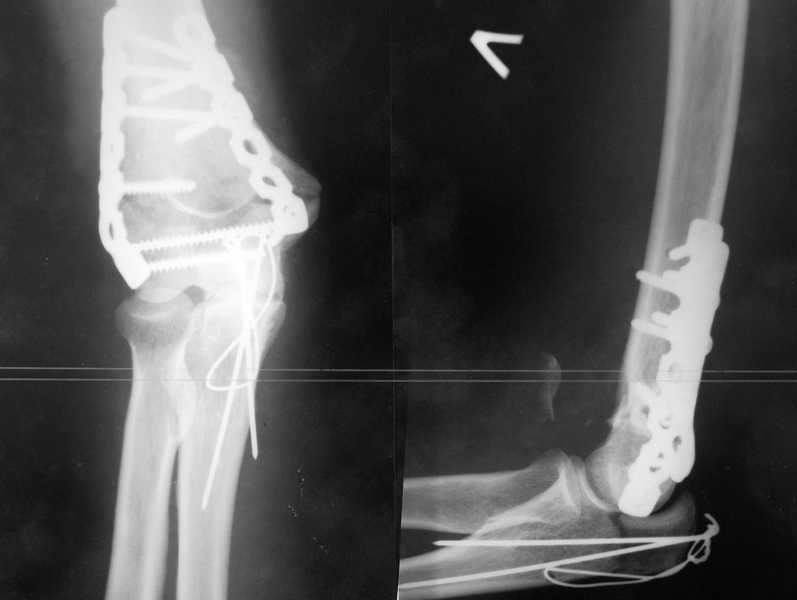

У пациентки 42 лет после операции остеосинтеза чрезмыщелкового перелома плеча, выполненной в нашей клинике 2 месяца назад, на контрольных R-граммах имеется гетеротопический оссификат по передней поверхности плеча. Оперирована по методике АО, после операции максимально рано начала заниматся ЛФК. В настоящее время основная жалоба пациентки на ограничение сгибания в локтевом суставе. Клинически объем движений: сгибание 90 градусов, разгибание 170 градусов, ротационные движения в полном объеме. Привожу снимки сразу после операции и через 2 месяца. (На рентгенограммах после операции в мягких тканях по передней поверхности плеча имеется небольшой костный фрагмент, но его ширина во фронтальной плоскости не более 1 мм., обнаружен был по снимкам после операции. Интраоперационно основные крупные фрагменты отрепонировались хорошо, объем движений был сгибание до 75 градусов, разгибание 175 град.) Пациентка неудовлетворена объемом сгибания, хотя была предупреждена о высокой вероятности ограничения движений. Профилактика гетеротопической оссификации (прием индометацина) не проводилась, т.к. имелась язвенная болезнь, да и эффект от его приема считаю сомнительным. Вопросы: 1.Стоит ли вмешиваться и пытаться удалить экзостоз? Если да,то в какие сроки и каким доступом лучше идти? 2. Оставить все как есть? 3. Не поможет ли ударно-волновая терапия либо какая-то другая методика? Буду благодарен за все ответы и оценки своей работы. С таким осложнением столкнулся впервые.

Снимки сделаны по правилам укладки, но объем сгибания сейчас 90 градусов. Пациентка хочет большего объема сгибания.